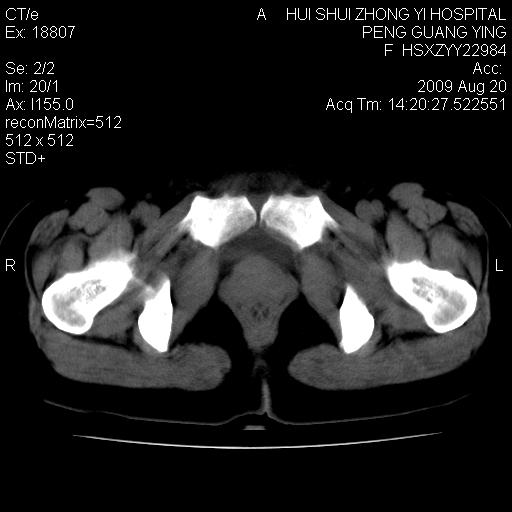

标题: CT21707:女,42岁,因发现下腹部包块2月。 [打印本页]

标题: CT21707:女,42岁,因发现下腹部包块2月。

目前的影像表现显示肿块位于腹腔及盆腔,但具体定位,分清来源较困难,是否来源于卵巢、子宫无法定论,子宫直肠及子宫膀胱周围脂肪间隙尚较清晰,如果患者有过腹腔好或者盆腔手术史,也可以形成不典型的血中,最好手术后定为定性,我期待结果。

软组织密度,与子宫一致。双侧卵巢形态、密度好,不支持来源于卵巢。